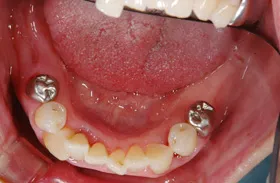

他院で「歯槽膿漏は治らない」と言われ、当院にご来院されました。歯が乱ぐいのため、歯並びもよくしたい、下は歯を既に失っているので噛めるようにもなりたい、またコーラスをされていて人前で口をあけることが多いので、できるだけ見た目を意識した治療をしてほしいとのご要望でした。

■治療前